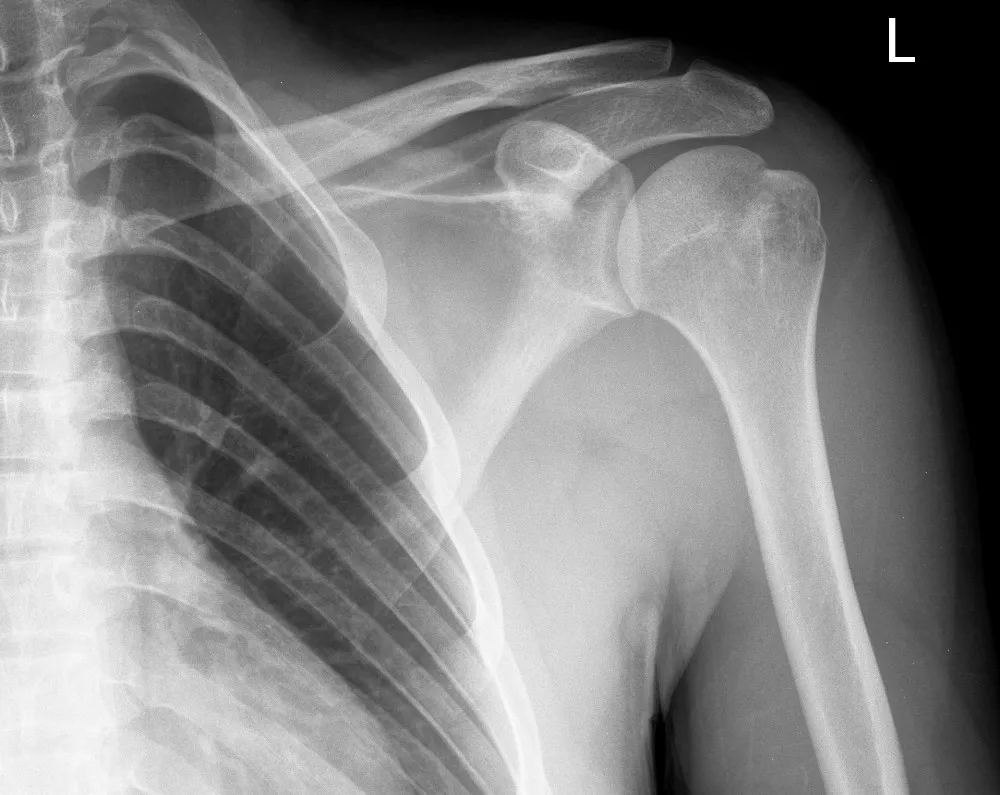

X ışını kamera. En basit şekliyle bir duvarında küçük bir delik bulunan karartılmış bir odadır. Dünyada ilk kez 2015 te kullanılan cihazın birinci versiyonu. Bir x ışını teleskobu xrt uzaktaki objeleri x ışını spektrumunda gözlemlemek için dizayn edilen teleskoptur. şiddetli kabızlık tedavisinde kolonu etkileyen sağlık problemlerinin tedavisinde kanser taramaları öncesinde doktorunuz tarafından önerilebilir.

en cok satan tibbi urunler x ray tibbi yazici x ray kamera tibbi x isini termal film yazici iyi fiyat ile buy tasinabilir x isini film yazicisi x

kore evet rayme x ray kamera evet biyoteknoloji dis rontgen unitesi dis tasinabilir x isini unitesi buy dis x ray kamera evet biyoteknoloji dis